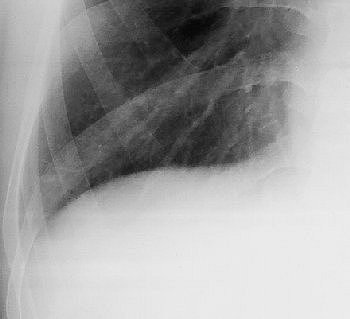

![]() |

| Image B. Magnified frontal chest radiograph, obtained eight months after image A, shows an ill-defined mass (arrow) above the right side of the diaphragm that is not evident in image A. The lesion was classified as radiographically uncertain in origin. |